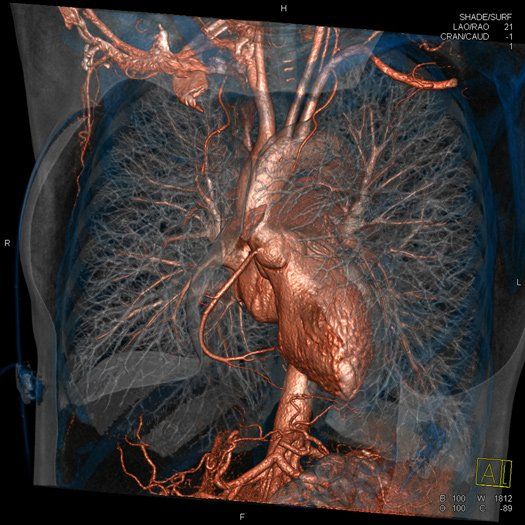

- КТ легких назначают при подозрении на туберкулез, рак легких, а также другие поражения в легких, трахеи, сосудах, наличие метастазов.

- КТ грудной клетки позволяет просматривать легкие и другие структуры этой области. Назначают при травматических поражениях, также туберкулезе, эмфиземе легких и других поражениях.

- Ангиография – аорты, сосудов, конечностей, шеи, головного мозга.

- Грудной клетки – бронхов, горла и гортани, легких.

Аппарат МСКТ из-за короткого времени сканирования позволяет избежать подобных артефактов, а легкие теперь обследуются всего за одну задержку дыхания. Внедрение ЭКГ-синхронизации, при которой срез делается только между сокращениями сердца, а также использование контрастного вещества позволило детально обследовать сердце, аорту и другие «пульсирующие» сосуды. Главное, достигнуто высокое пространственное разрешение с возможностью сканирования в любой плоскости с построением трехмерных изображений, что позволило аппарату МСКТ показывать онкологию с точностью до 0,5 мм, исследовать даже самые мелкие метастазы и выявлять распространенность процесса.